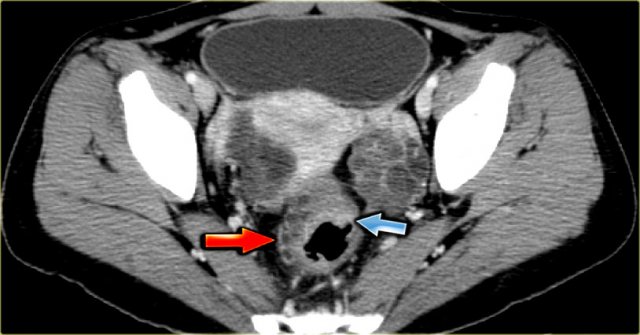

Hemorrhagic ovarian cyst Hemorrhagic ovarian cyst

The ultrasound images show multiple simple and one complex right ovarian lesion (red arrow).

The latter demonstrates diffuse low-level echos and no flow on Doppler.

Note that there is a good through transmission (blue arrow).

These findings indicate the presence of a hemorrhagic cyst.

Continue with the MR-images.